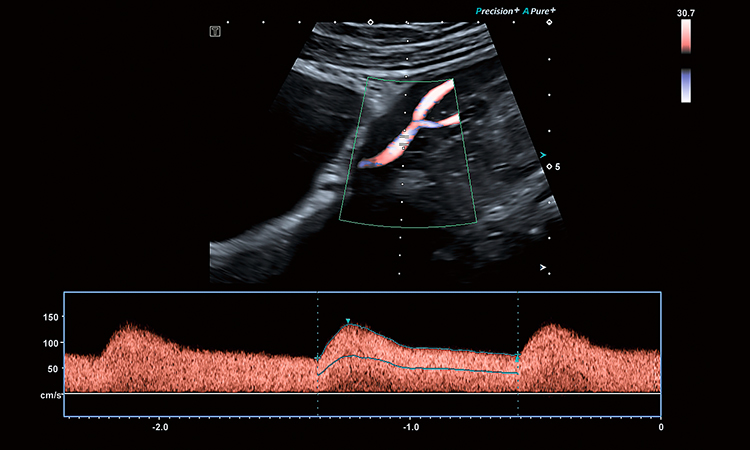

Shear Wave Elastography per valutazioni tissutali quantitative

Advanced Doppler per flussi lenti e microvascolarizzazione

Funzionalità di auto-update Doppler PW/CW